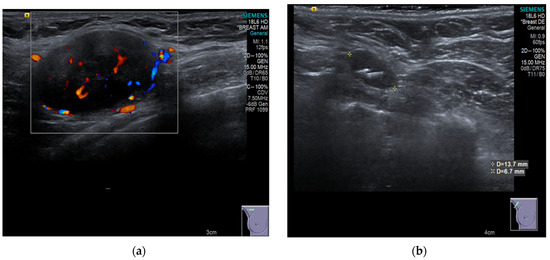

4.3. Imaging Modalities for Axillary Monitoring